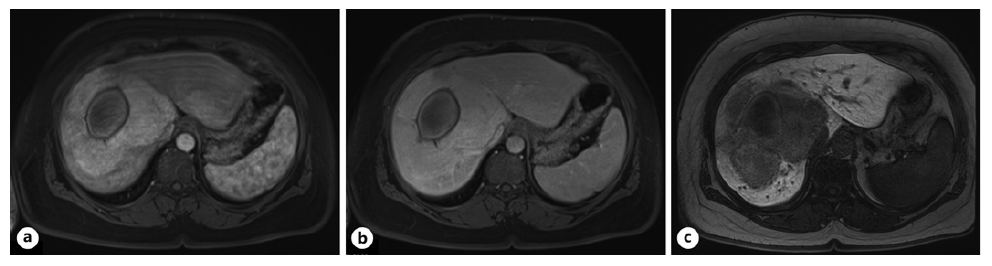

Further workup revealed negative serologies for hepatitis B and C virus. Regarding tumor markers, alpha-fetoprotein, carcinoembryonic antigen, and carbohydrate antigen 19-9 were within normal range (shown in Table 1). To determine etiology, an abdominal MRI with hepatobiliary-specific contrast was performed, with findings compatible with a 7.2 × 6.1 × 4.6 cm HCA, more likely inflammatory or hedgehog subtype (shown in Fig. 3). The patient was discussed in a multidisciplinary team meeting, and surgery was proposed.

Fig. 3 Abdominal MRI with hepatobiliary-specific contrast. Peripheral solid component showing enhancement on arterial phase (a), isointense (no washout) on portal phase (b), and hypointense on hepatobiliary phase (c) mass with 7.2 × 6.1 × 4.6 cm in segments VII, VIII, and I with a central hematic area secondary to the previous bleeding, suggestive of an HCA, more likely inflammatory or hedgehog subtype.